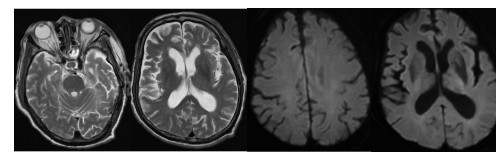

辅助检查:白细胞计数15.0×109/L,中性粒细胞百分比97.9%,淋巴细胞绝对值0.14×109/L,血小板计数344×109/L,血红蛋白94 g/L;降钙素原1.22 ng/mL,白介素6 87.5 pg/mL,C-反应蛋白254.5 mg/L;丙氨酸氨基转移酶171 U/L,天门冬氨酸氨基转移酶292 U/L,白蛋白24.7 g/L,肌酐186 μmol/L,尿素氮18.99 mmol/L,B型钠尿肽前体(pro brain natriuretic peptide, pro-BNP)3 301 pg/mL。胸部CT示两肺炎症渗出,左肺实变(图 1A)。经验性予美罗培南0.5 g每8 h一次联合莫西沙星400 mg每24 h一次抗感染治疗。行支气管镜检查留取肺泡灌洗液送痰培养和mNGS检测。在患者入院第2天,外周血mNGS检测到鹦鹉热衣原体,序列数166。改用美罗培南0.5 g每8 h一次(第1~10天)和多西环素片口服100 mg每12 h一次(第2~18天)抗感染治疗(图 2)。入院第3天的肺泡灌洗液mNGS回报鹦鹉热衣原体(序列数280)。痰培养、血培养、血隐球菌抗原、真菌G/GM试验均为阴性。入院第4天行腰椎穿刺检查,测得压力为240 mmH2O(1 cmH2O=0.098 kPa),脑脊液为无色透明,留取标本送常规、生化和mNGS。脑脊液结果提示有核细胞数为2×106/L,红细胞计数为22×106/L(参考范围 < 1×106/L),蛋白含量为34.8 mg/dL(参考范围8~43 mg/dL),葡萄糖含量为4.13 mmol/L(参考范围2.2~3.9 mmol/L)。入院第6天,脑脊液mNGS结果回报鹦鹉热衣原体(序列数4)。入院第8天复查腰椎穿刺的压力为185 mmH2O,留取标本送检。本次脑脊液常规和生化结果与第一次相仿,mNGS未检测到鹦鹉热衣原体。经过抗生素治疗(图 2),患者一般情况好转,炎症指标下降(图 3A、3B),脏器功能好转(图 3C、3D),复查胸部CT提示肺部病变吸收(图 1B),于入院第11天拔除气管插管改鼻塞吸氧,氧合99%,生命体征平稳。神志清,对答切题,语言流利,颈软。能稳准地完成指鼻试验和跟-膝-胫试验。于入院第18天出院。后随访患者恢复良好,无后遗症。住院期间头颅磁共振提示腔隙性缺血灶,未提示新发脑梗、脱髓鞘等病变(图 4)。患者出院后第5天和第44天查胸部CT见左肺渗出进一步吸收(图 1C、1D)。

| 图 4 患者住院期间头颅磁共振平扫与弥散成像影像 |